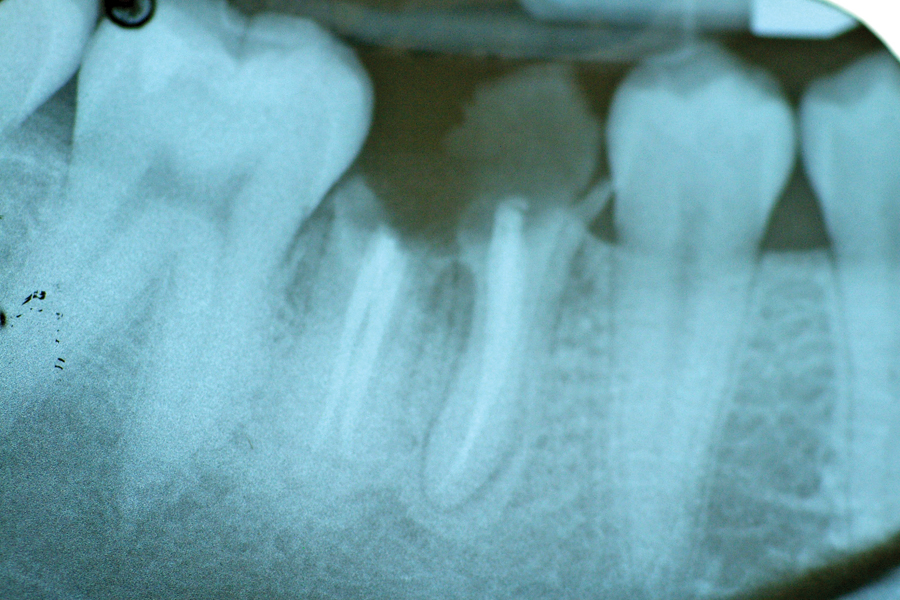

Mrs. Jones and her husband presented to my Prosthodontic Specialty clinic for an additional opinion regarding her treatment options to improve her existing oral condition. After conducting an interview with Mrs. Jones and completing a comprehensive clinical examination, along with diagnostic records, I presented three potential treatment plans. The advantages and disadvantages, risks and benefits … Read more